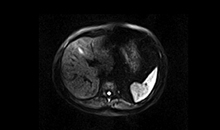

Uygulama Görüntüleri